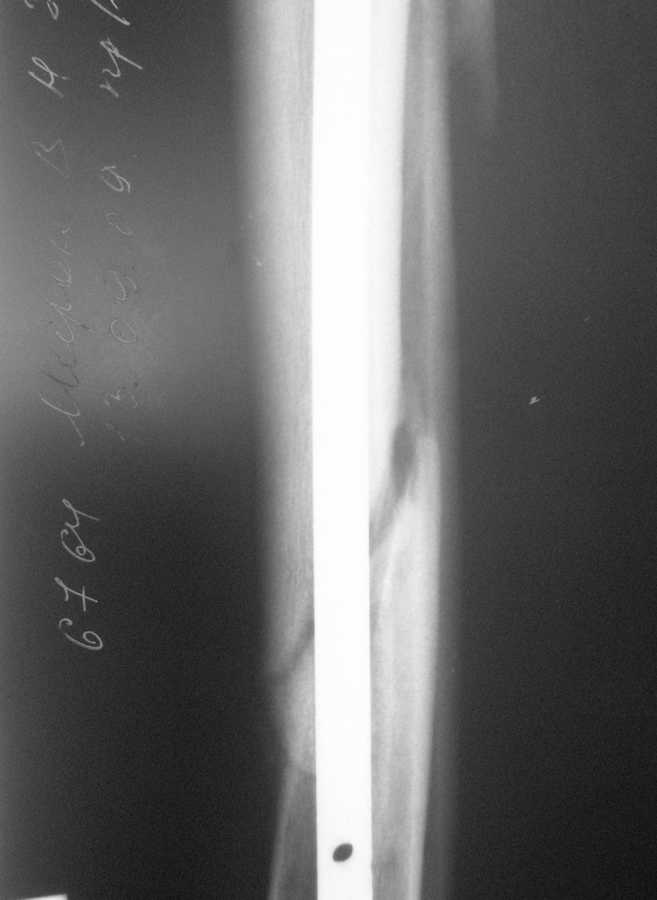

В январе 2009 года нами оперирована пациентка с переломом н\3 голени штифтом Expert. Динамизация через 4 месяца, пациентка при этом уже ходила с тростью. Дома периодически передвигалась без дополнительной опоры.

В настоящее время - через 9 месяцев с момента операции периодически в вечернее время беспокоят ноющие боли в места перелома (не постоянно). При беседе выяснено, что боли чаще беспокоят после того, как днем она походит по дому без трости. Пальпаторно по гребню берцовой кости болей нет, но по задне-внутренней поверхности б\б кости пальпирутеся западение на уровне места перелома.

Имя     : через 9 месяцев (1).jpg

Тип     : image/jpeg

Размер  : 20666 байтов

Описание: отсутствует

Url     : http://weborto.net:8080/pipermail/ortho/attachments/20090913/ceda924c/attachment-0003.jpg